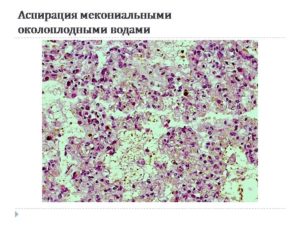

Медицинские аспекты мекония в околоплодных водах